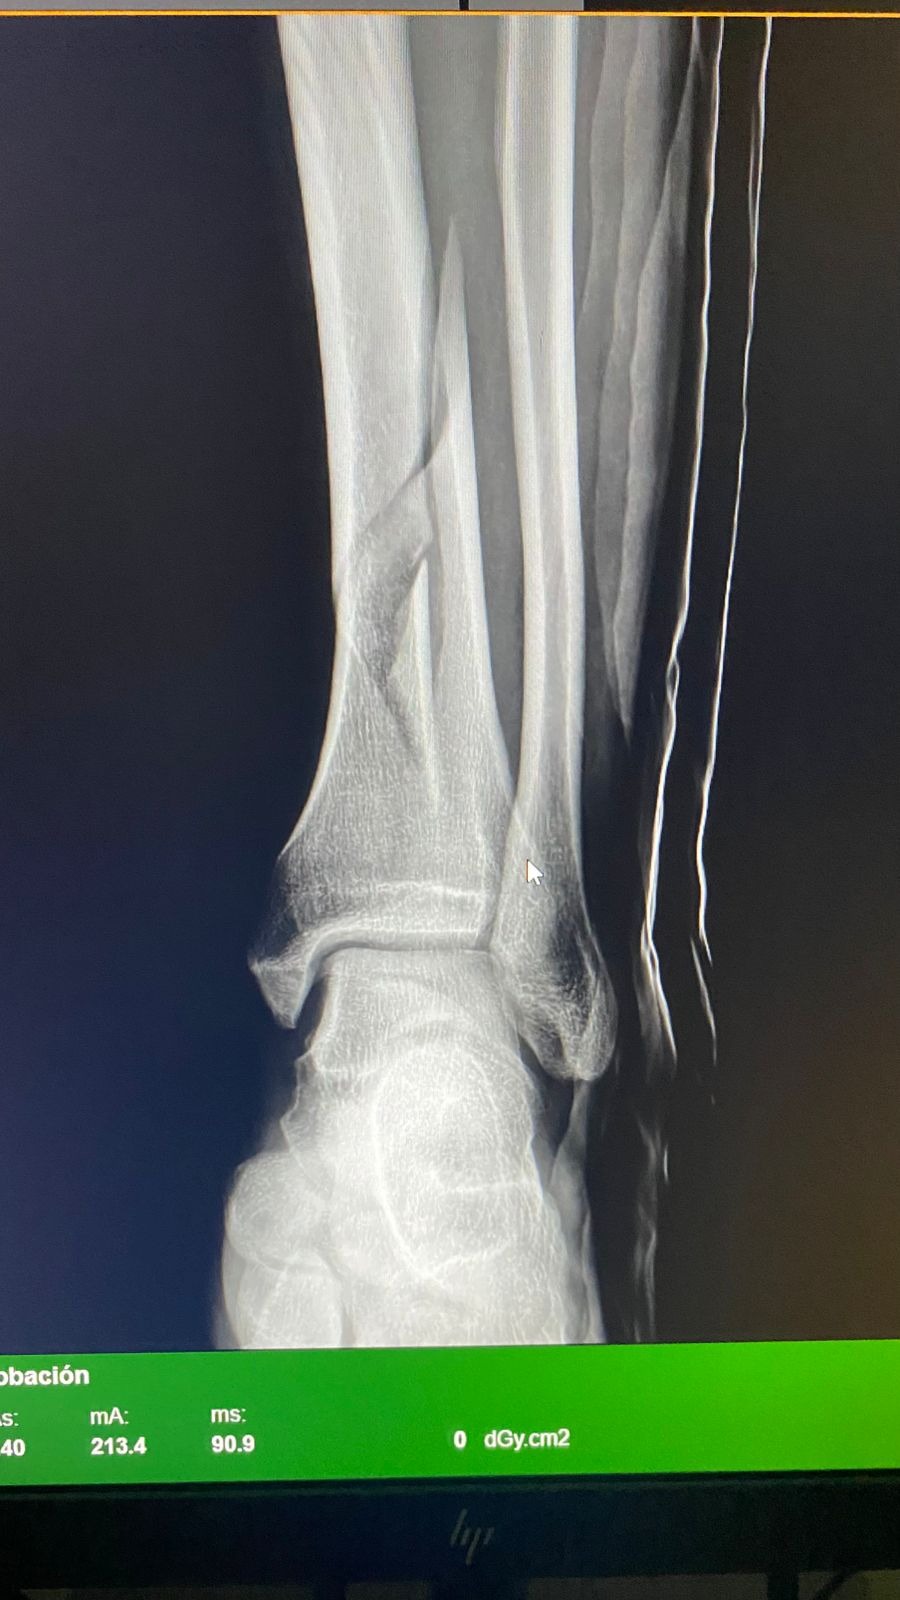

My name is Rafael Benson Arellano. I’m a local resident and small business owner working alongside my brothers in our family business. Recently I was involved in a serious motorcycle accident that left me with a broken leg and required emergency surgery and hospitalization in La Paz.